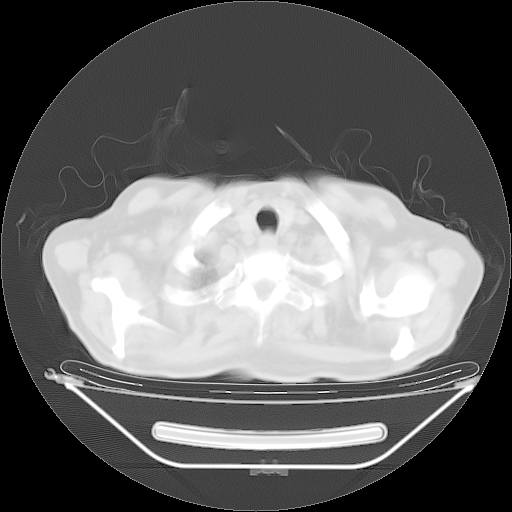

今天复查肺部CT,发现双肺广泛磨玻璃样改变。所以我把3月19日和5月9日相隔50天的肺部CT上传。请大家会诊。

2009年3月19日肺部CT片。

2009年3月19日肺部CT